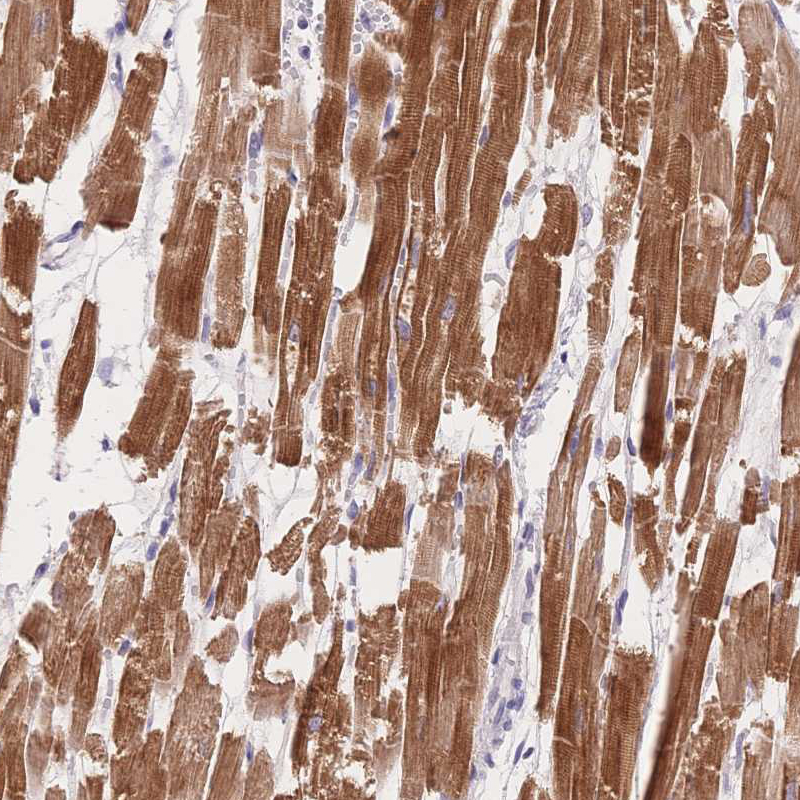

Immunohistochemistry analysis in human heart muscle and pancreas tissues using HPA049193 antibody. Corresponding MYOM1 RNA-seq data are presented for the same tissues.